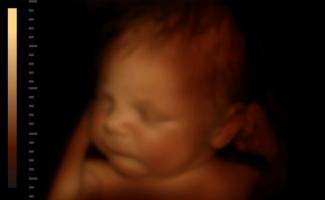

‘Brain dead’ Georgia mother delivers 1-pound baby boy after 4 months on life support